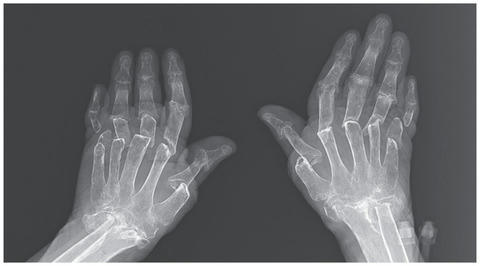

米マサチューセッツ内科外科学会が発行する医学誌『ニューイングランド・ジャーナル・オブ・メディシン』に今月11日に掲載された症例報告によると、この女性は両手の指がどんどん短くなるという病気で、トルコの首都アンカラにあるガーズィ大学病院を訪れた。

リウマチ科のハサン・サーティス医師によると、女性は18年前の50歳当時に関節リウマチと診断を受けて以来、グルココルチコイドやメトトレキサートなど、さまざまな薬を試したが、どれも効果がなく、両手の指がかなり変形していた。

痛みは手指だけではなく、手首から肘、両膝、足首などあらゆる関節に圧迫痛と腫れがあった。

レントゲン写真に映し出された両手の骨は、破壊がかなり進んでいて、すべての指の第二関節が本来の位置からずれて脱臼しており、指の曲げ伸ばしができない状態だった。

サーティス医師は

「破骨細胞の異常によって、急速に骨が溶けたために、指がめりこんでいる」

と診断。骨が溶ける速さに追いつかなかった皮膚が、膝まで下げたズボンのように、ゆるゆると骨にまとわりついているほどだという。